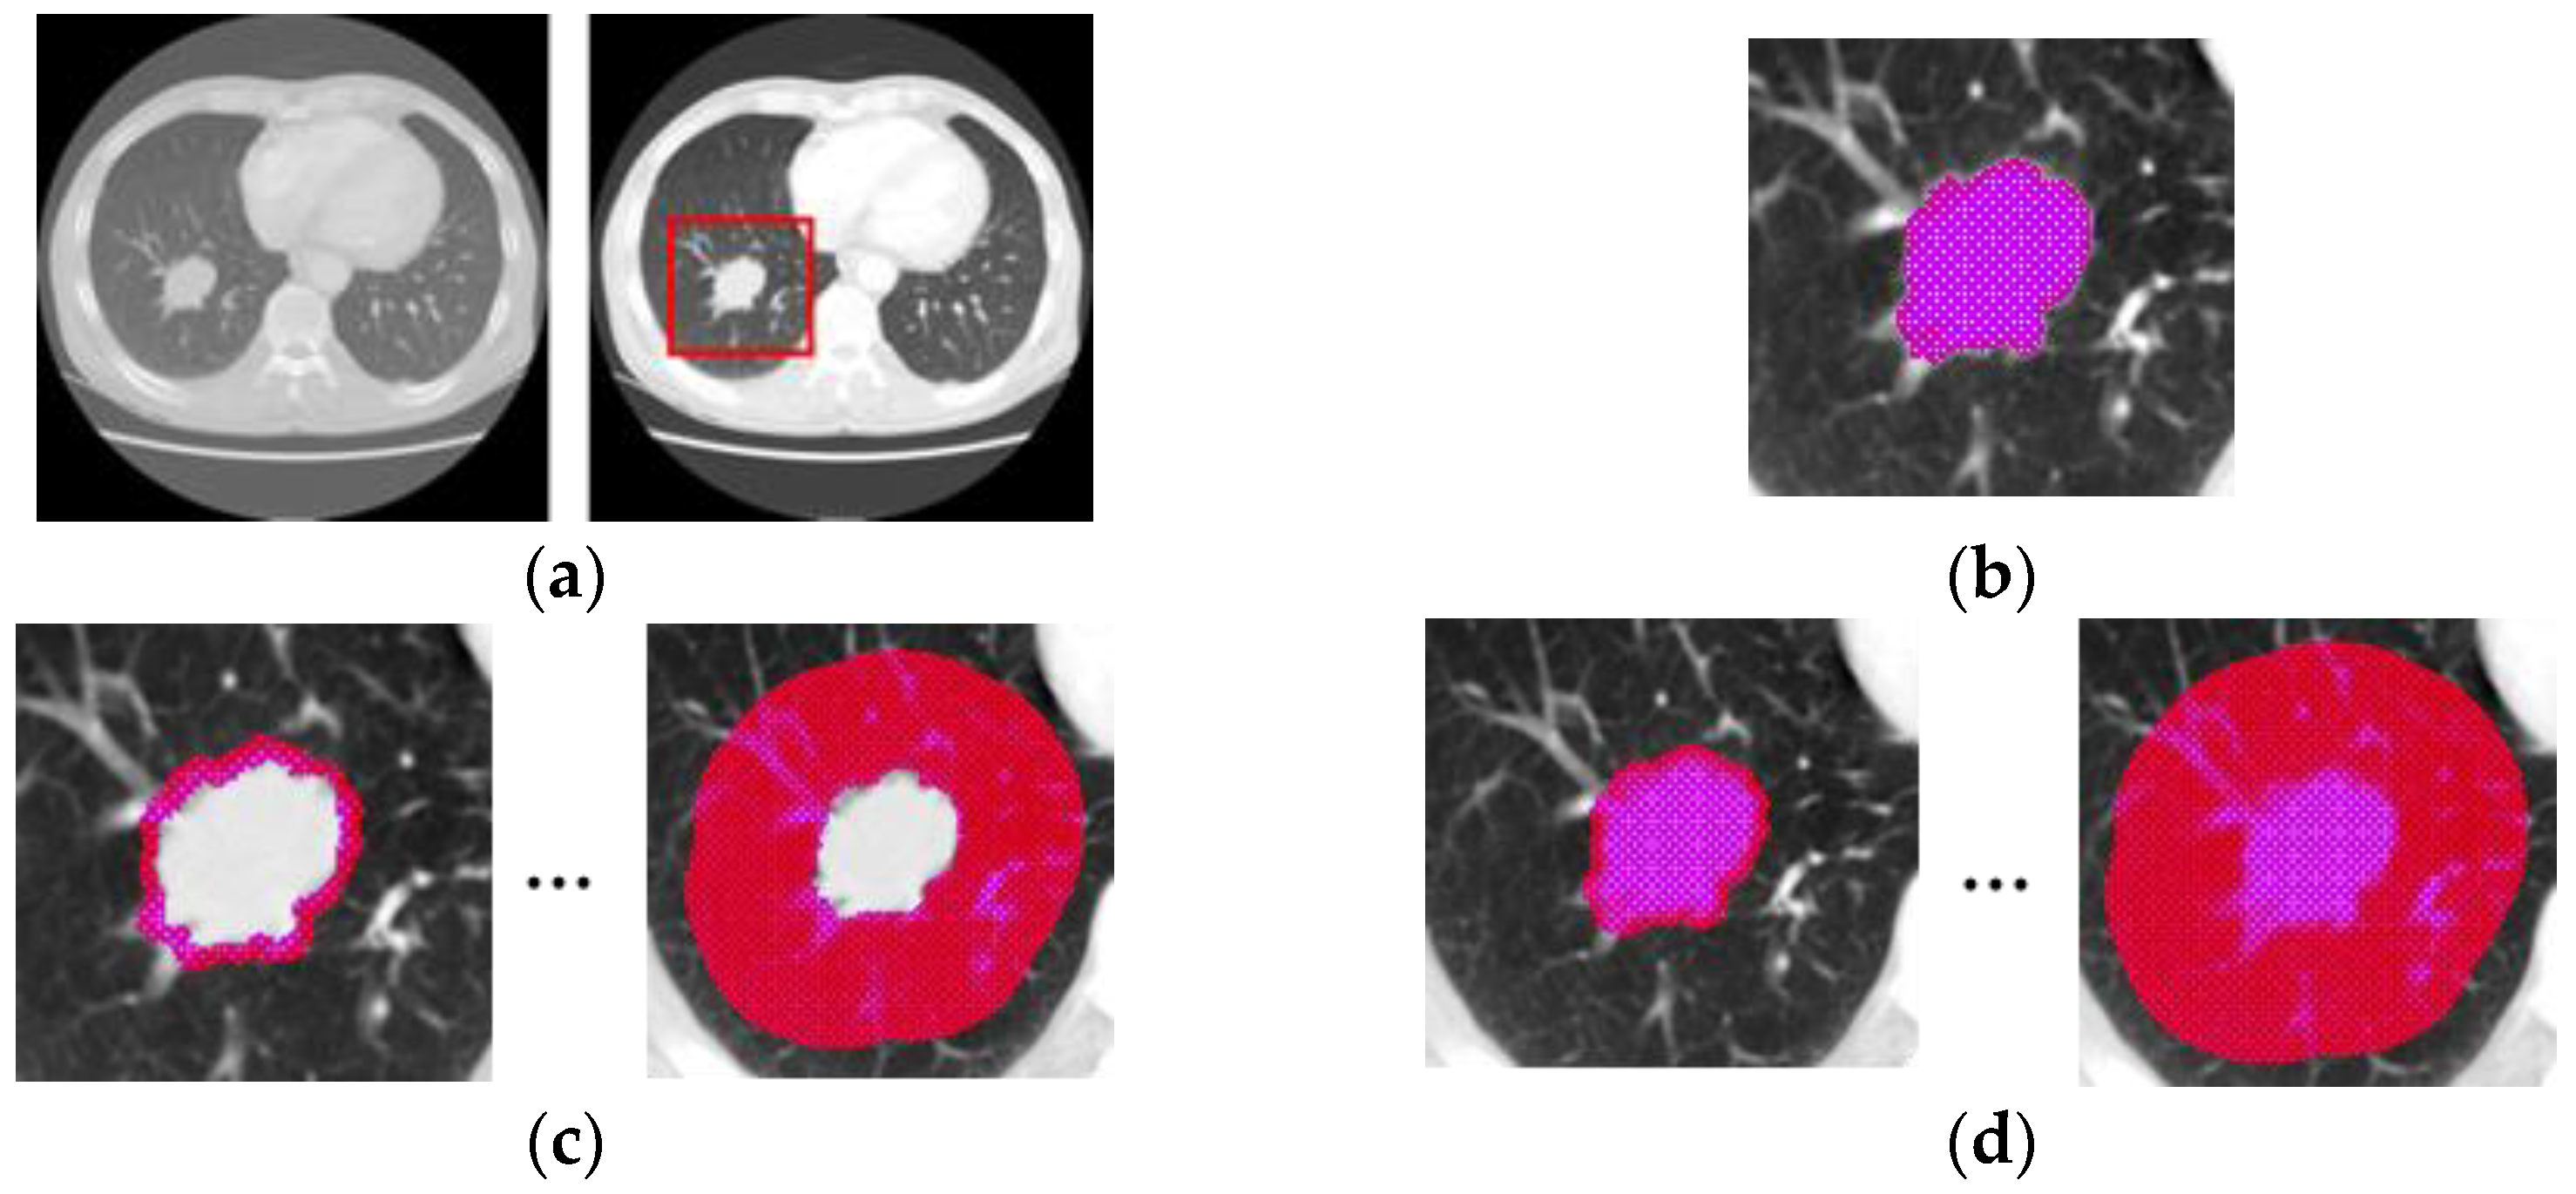

2.2. Data Preparation